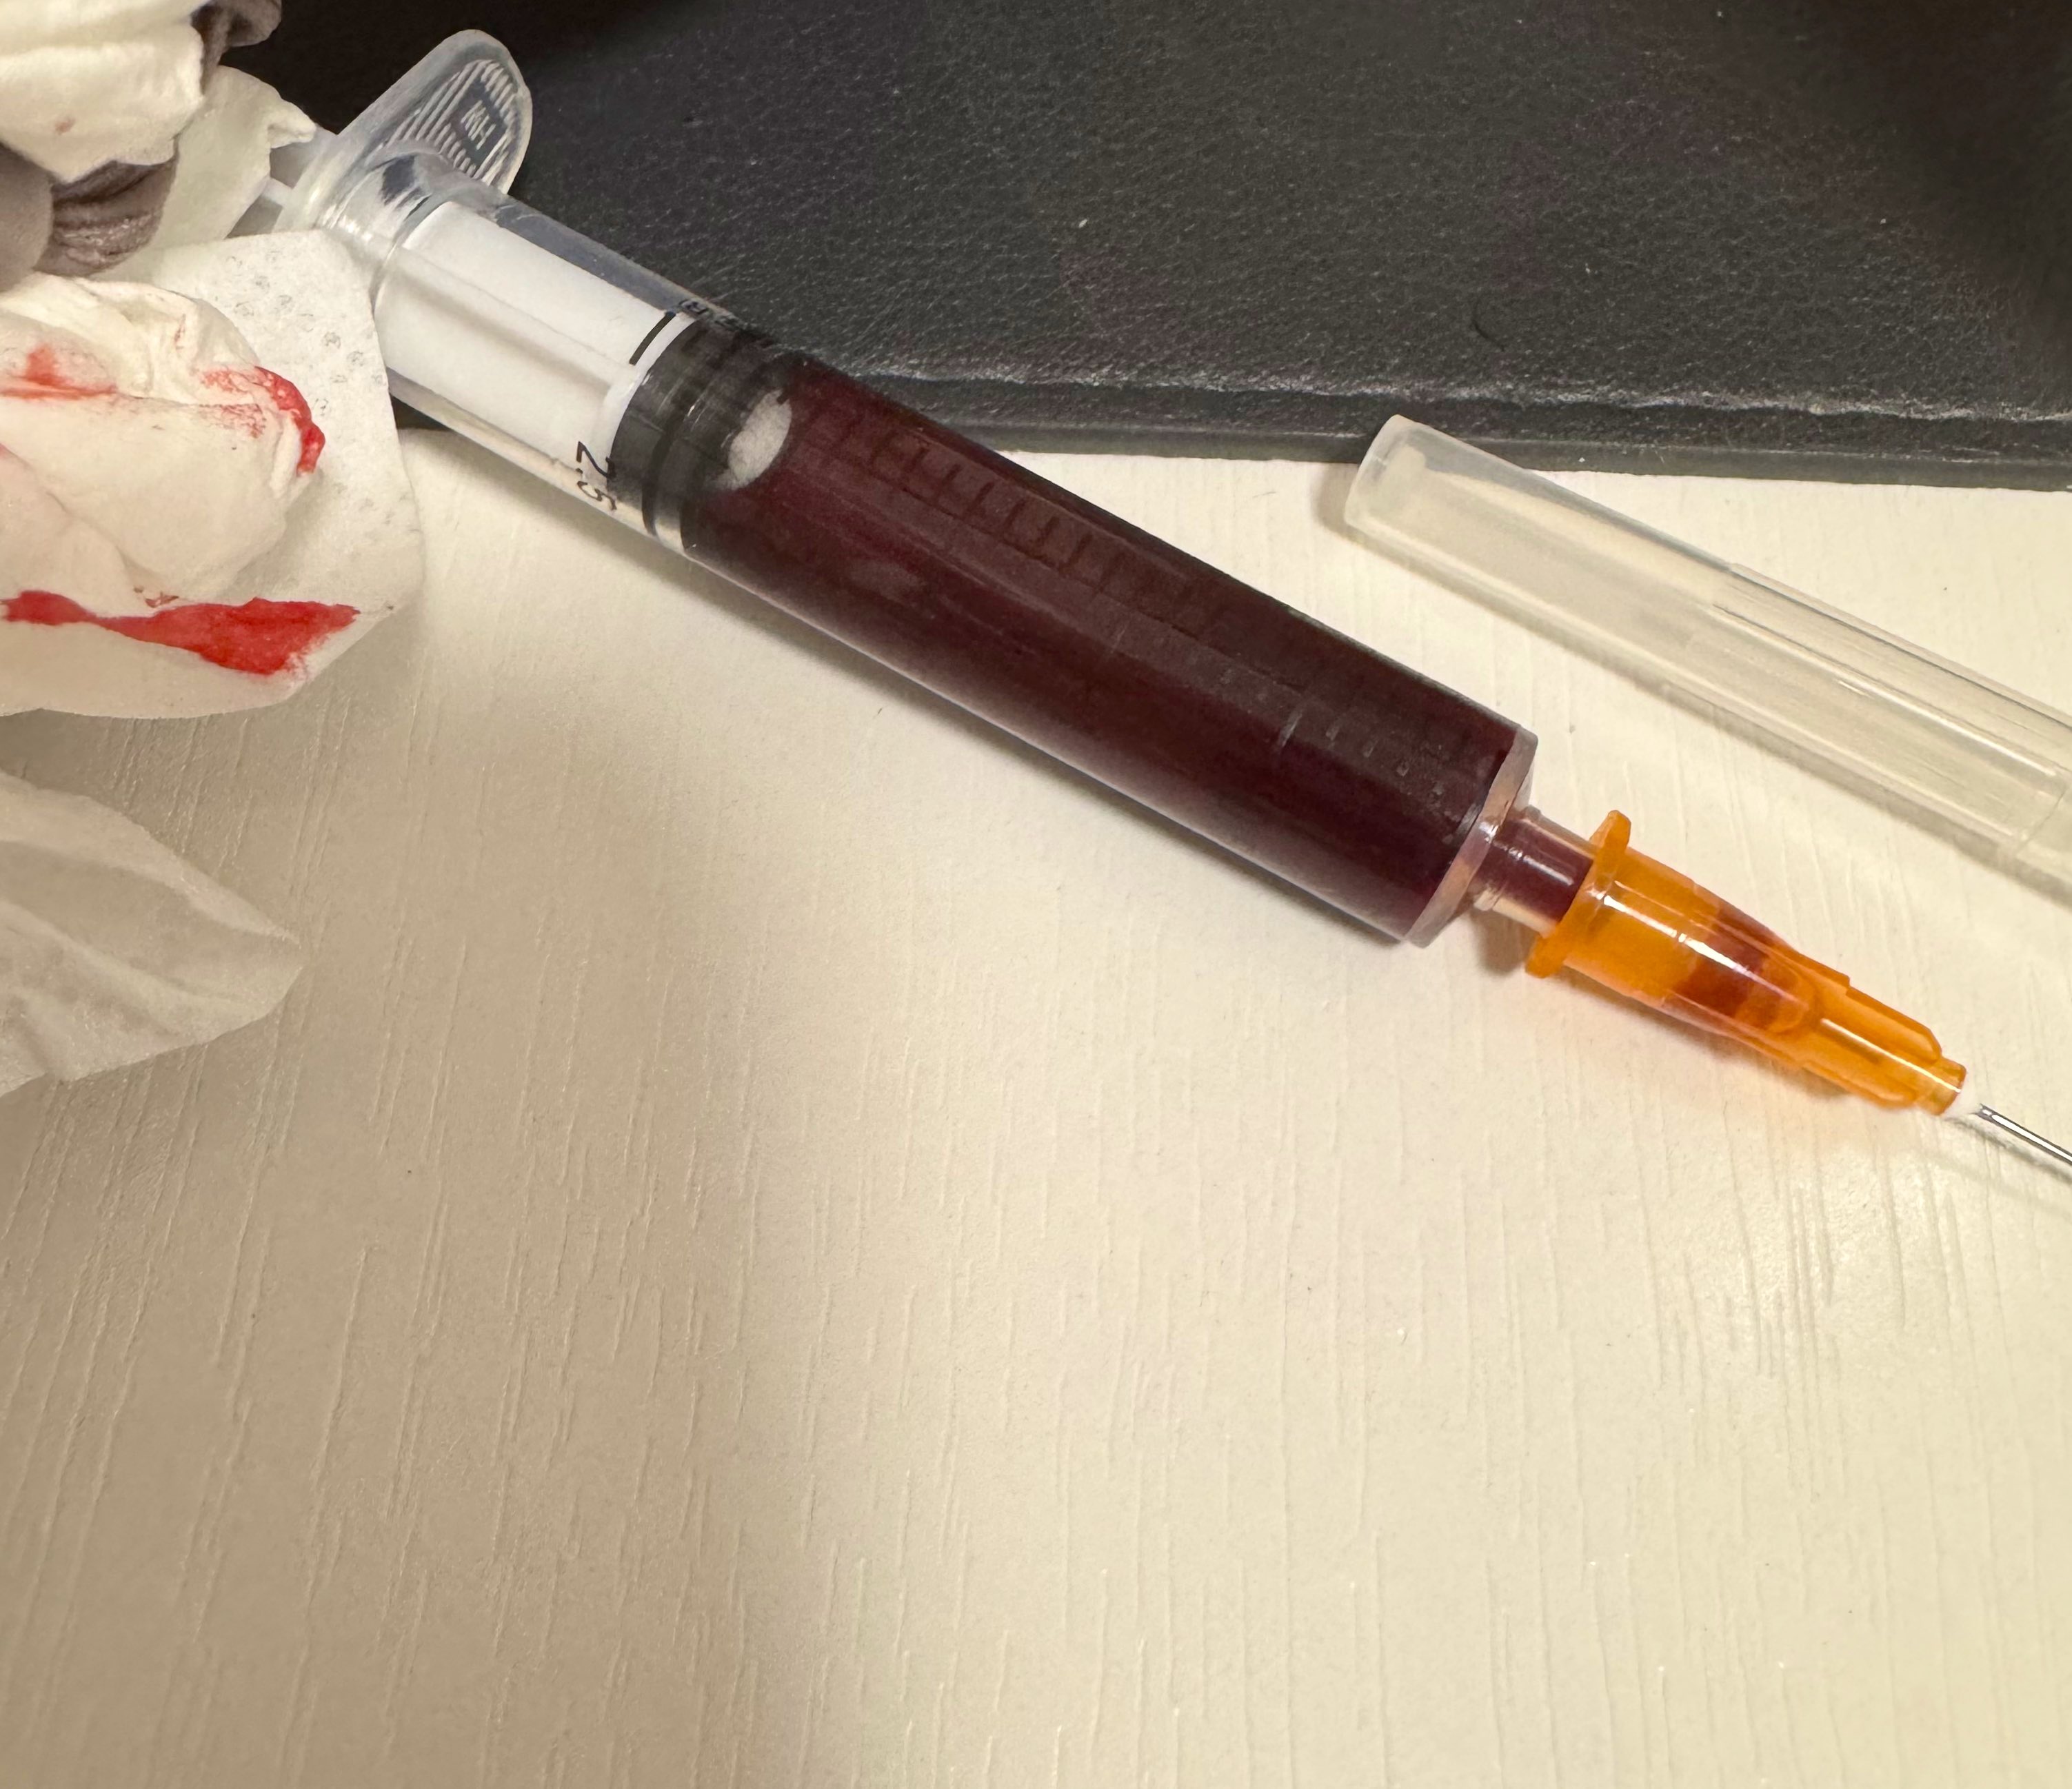

吃完唑吡坦会干一些难绷的事情,昨天睡不着疑似气急败坏了抽了0.5ml右美托咪定就是iv,还奇奇怪怪挑了个很痛的头静脉

后面不记得了,醒了灯开着的还以为是做梦,对着针孔一脸不可置信地整理记忆

你别说还扎得挺好的()按压时间估计也够,一点淤青也没有,不知道哪来的意志力 https://t.co/KxtfAUVSmb

炽烈已极 @AnIncandescenceMOR可能因为耐受,第一次给药把受体占满了第二次几乎无效,羟考酮作用在压型κ的那一部分让头晕恶心更明显,几乎没有体会到什么正面作用,和之前被包裹在温暖和安心中停下呼吸也没有窒息感不同,它会让我困得撑不住又被呼吸暂停的缺氧憋醒,有点坏了

炽烈已极 @AnIncandescence@rainyosora 无所谓,有纳洛酮但不想吃,就这么耗着吧。不过我已经被折腾清醒了。

想喝掉。 https://t.co/lVy6kkZzgX2026-03-19 10:05:38 UTC